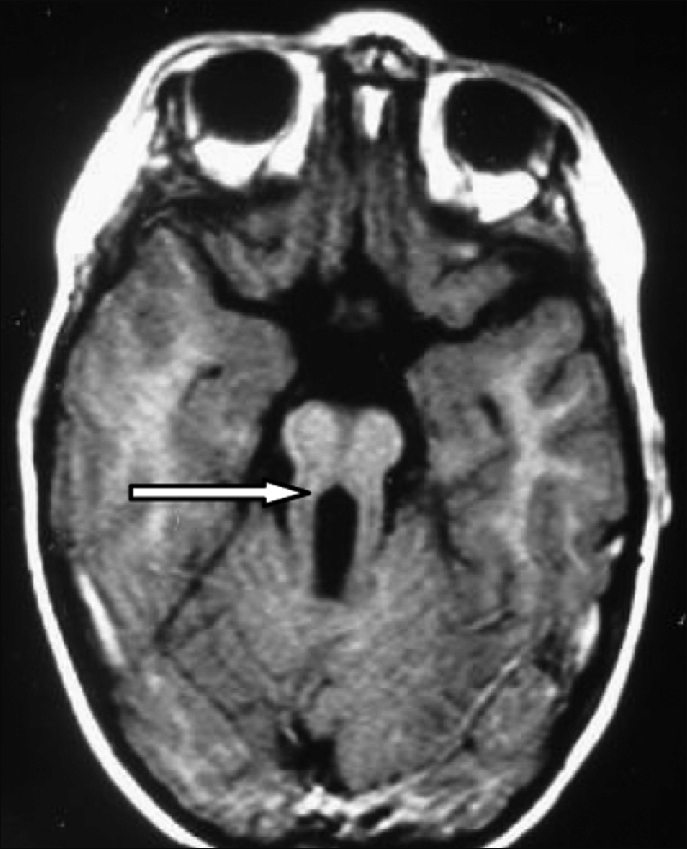

A quanto ho appreso leggendo qualche pagina su questa malattia, la discinesia ciliare si accompagna spesso alla sindrome di Joubert, un disturbo che è caratterizzato dalle malformazioni o dal sottosviluppo di alcune aree del cervelletto. È facilissimo identificarlo con una risonanza magnetica, perché le immagini evidenziano una malformazione del mesencefalo/romboencefalo che ha un aspetto assolutamente caratteristico: è quello che, per ottime ragioni, i medici chiamano «segno del dente molare».

Insomma, se davvero “Dracula” era affetto da discinesia ciliare primaria, è possibile che avesse letteralmente una cosa sola in testa: un gigantesco “dente fantasma” dove non avrebbe dovuto esserci. Perdipiù, ci sono ottime probabilità che soffrisse di situs viscerum inversus, ovverosia avesse il cuore nella parte destra del torace.